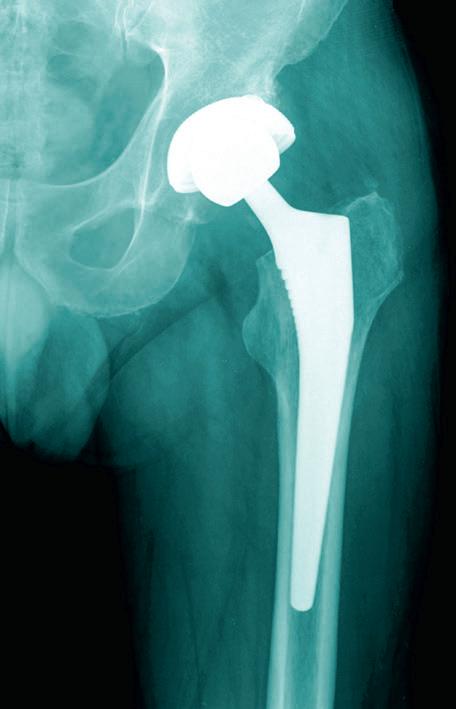

104 Hip, Hop, Don’t Stop

Is hip pain slowing you down? Replacing a painful joint is becoming faster and easier as medical technology improves